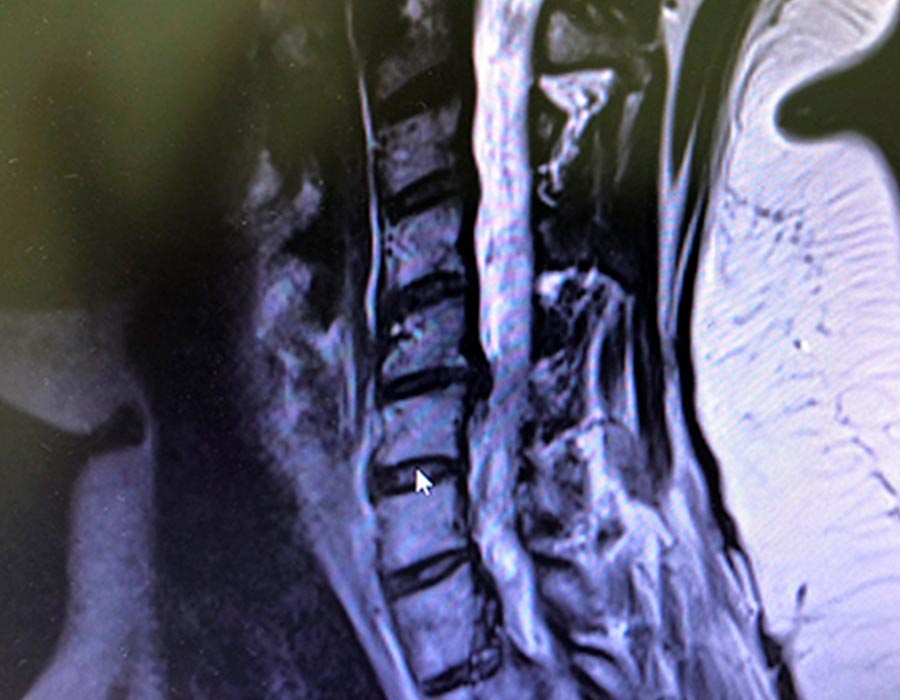

Operación

Procedemos a realizar una cirugía donde retiramos la hernia y le colocamos un disco completamente móvil, a través de una incisión de 2 cm a nivel de la piel.

Cirugia hernia discal postoperatorio

Postoperatorio

La paciente no tiene síntomas de dolor, sin Parestesias en el brazo izquierdo, y nos cuenta que le ha desaparecido la sensación de presión constante que tenía en la zona de la nuca.

La cirugía con resultado satisfactorio y una recuperación inmediata en menos de 24 horas. La paciente puede realizar su vida completamente normal e iniciar la rehabilitación en 4-5 días.